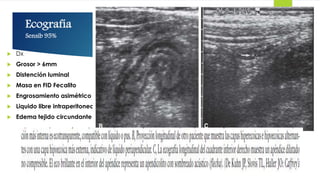

Ecografía

Sensib 95%

 Dx

 Grosor > 6mm

 Distención luminal

 Masa en FID Fecalito

 Engrosamiento asimétrico

 Liquido libre intraperitoneal

 Edema tejido circundante

Ecografía Sensib 95%  Dx Grosor > 6mm  Distención luminal  Masa en FID Fecalito  Engrosamiento asimétrico  Liquido libre intraperitoneal  Edema tejido circundante